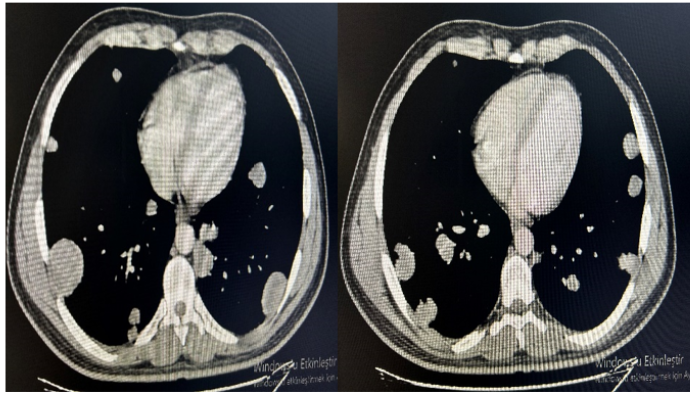

Asymptomatic Testicular Carcinoma Presenting with Metastatic Pulmonary Symptoms: Case Based Review

Cuneyt Tetikkurt, Başak Toksöz and Bilun Gemicioğlu. 12(3): 30-36.